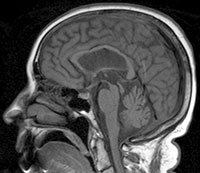

การวินิจฉัย PSP อาศัยการซักประวัติและตรวจระบบประสาท ร่วมกับการตรวจภาพสมอง เช่น MRI เพื่อตรวจหาการฝ่อของสมองส่วน midbrain ซึ่งอาจเห็นเป็นลักษณะ hummingbird sign รวมถึงการตัดโรคอื่นที่มีอาการคล้ายกันออก